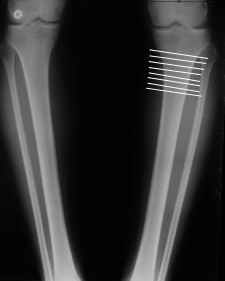

AC> Обратилась дама 25 лет. Вынуждена ходить в брюках из-за genu varum,

AC> что побудило обратиться за коррекцией.

Судя по снимку у девушки имеется внутренняя установка надколенников...

Как у нее с торсионным статусом? Бедро? Голень? КТ? Торсиометры? А то, куда будут

смотреть надколенники после вашей коррекции - тоже существенный

косметический момент. Или не так?

AVM> Судя по снимку у девушки имеется внутренняя установка надколенников...

AVM> Как у нее с торсионным статусом? Бедро? Голень? КТ? Торсиометры?

Похоже, немного есть. Думаю пренебречь.

Отправитель: T. Derek V. Cooke 13 Сентябрь 2005, 23:51

|

Hello Alex:

Thanks for the clinical photo.

Your patient appears to have "Insquinting Knees"?

I am attaching a word doc with a 'print screen' of the program in use, showing the images being viewed and analysed

. On the right leg you can see some of the tools (from the tool bar above) applied to demonstrate a mild mech-axis varus of about 5 degrees.

On the left the bone landmarks used in the anlaysis are shown.

The data for the analysis are in the XLs sheet below, exported from the program automatically.

I have given a label of the abreviations and some normative values.

In essence she has a mild mech-axis varus of 7 degrees with some contribution from the femur (2) degrees and more from the tibia (6 degrees), none from the joint.

The analysis took about 6 mins.

Regards

Derek